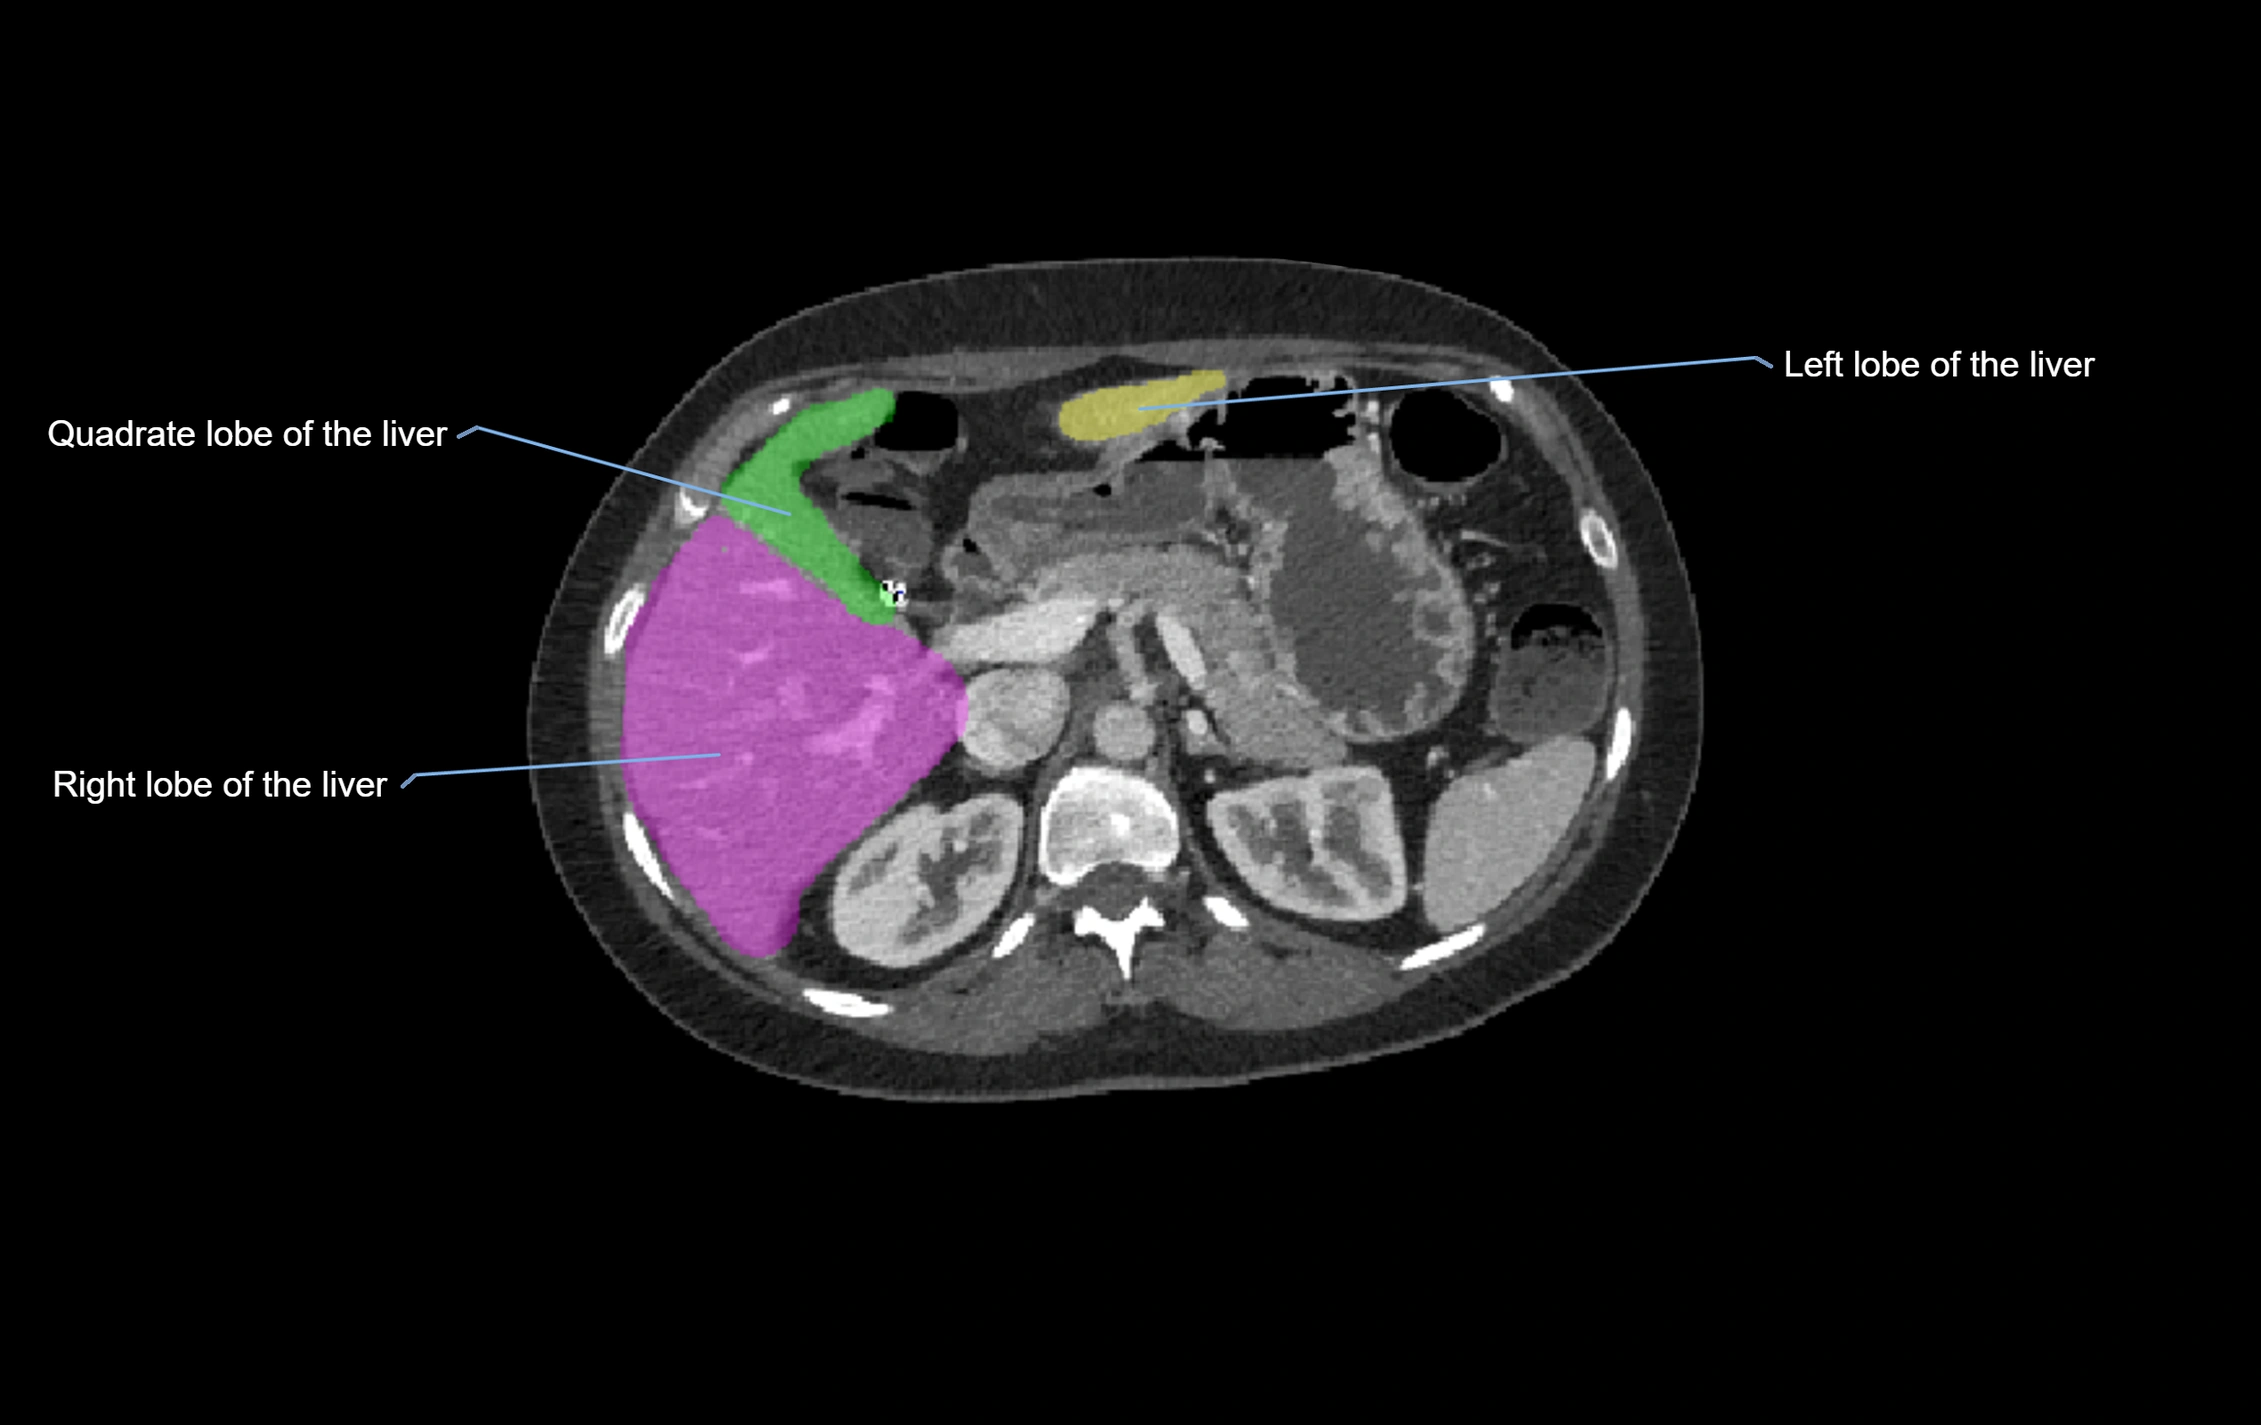

The caudate lobe of the liver is a distinct anatomical subdivision of the liver, designated as segment I in Couinaud’s classification. It lies on the posterior surface of the liver, between the fissure for the ligamentum venosum (left boundary) and the groove for the inferior vena cava (IVC) (right boundary). Superiorly, it is related to the posterior liver surface, and inferiorly it is separated from the left lobe by the porta hepatis.

image

CT Image